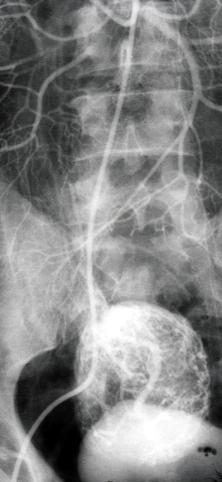

疾病(病理主体)的分类恶性非上皮性肿瘤/平滑肌肉瘤

部位(按器官分)小肠/空肠

检查方法X线

肿瘤最大直径40以上